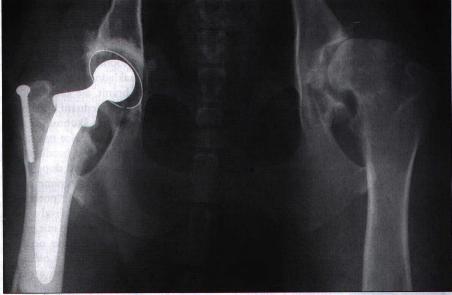

snížením funkčnosti kyčelního kloubu. Ve stadiu příprav (u nás) a

finančně náročnější je totální náhrada kyčelního kloubu, která se

zpravidla fixuje cementem. V této době je to nejpřijatelnější řešení

problémů doprovázejících dysplazii. Její provádění je u nás ale skutečně

ojedinělé. Je velice náročné na erudovanost operatéra a sterilitu

operačního prostředí. Pro zajímavost v Anglii tato operace vyjde na cca

6700 DM.

Protéza kyčelního kloubu na RTG snímku

(Gutbrod, Norimberg v Svět psů 10/99: 24-25).

Vzhledem k pokročilé artróze tento pes před operací silně kulhal. Po zákroku bylo možno operovanou nohu zase bezbolestně zatěžovat. Později byl úspěšně vyměněn i druhý kyčelní kloub. |